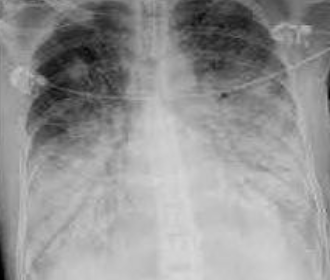

Patrón de vidrio esmerilado / despulido IMAGEN

Puedo ver los vasos sanguíneos en opacidad